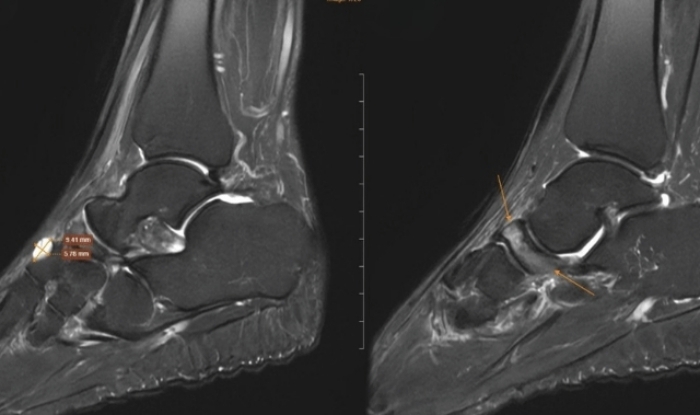

Tại cơ sở y tế, bác sĩ chỉ định chụp cộng hưởng từ để đánh giá tổn thương sâu. Kết quả, xương ghe bàn chân phải bị xẹp và biến dạng điển hình, kèm đặc xương dưới sụn và phù tủy rõ rệt. Ngoài ra, hình ảnh còn ghi nhận tổn thương thoái hóa khớp cổ chân trái, phù tủy xương sên, viêm dây chằng và dịch khớp cổ chân.

Từ sự phối hợp giữa lâm sàng và chẩn đoán hình ảnh, bệnh nhân được chẩn đoán theo dõi hội chứng Muller-Weiss bên phải, kèm phù tủy xương sên trái. Bác sĩ chỉ định điều trị nội khoa, tiêm huyết tương giàu tiểu cầu hai chân dưới hướng dẫn siêu âm, đồng thời sử dụng đế giày chỉnh hình. Sau điều trị, tình trạng đau giảm rõ rệt và khả năng vận động cải thiện.

Bác sĩ chẩn đoán hình ảnh cho biết việc phát hiện bệnh phụ thuộc nhiều vào các phương tiện cận lâm sàng. X-quang có thể cho thấy xương ghe biến dạng dạng dấu phẩy hoặc xẹp nhỏ. Chụp CT giúp đánh giá rõ tình trạng xơ cứng và phân mảnh xương. Cộng hưởng từ được xem là phương pháp nhạy nhất, phát hiện sớm phù tủy xương trước khi hình thái xương thay đổi, đồng thời đánh giá mức độ hoại tử.